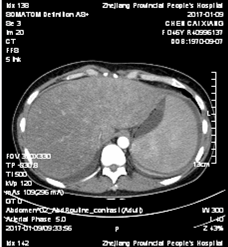

全腹增强CT:胸、腹腔积液;脂肪肝;慢性胆囊炎表现;脾脏体积增大;肠系膜区、腹膜后、子宫旁可见多发淋巴结显示(图1)。

图1